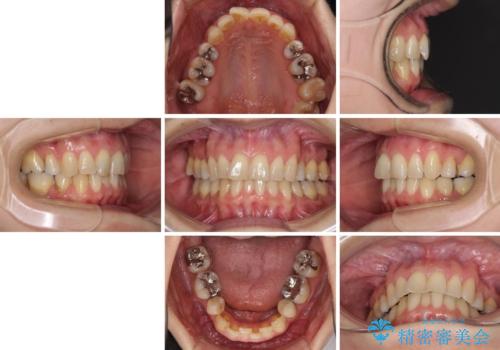

矯正の後戻りの改善と銀歯をセラミックに

- 矯正装置

- インビザライン・ライト

- 治療期間

- 1年1ヶ月

- 上下前歯の叢生を気にして来院された患者様です。

費用を抑え、期間もあまりかけずに治療をしたいとのことで、インビザライン・ライトを用いて矯正治療を行うこととしました。

矯正治療後には、下顎臼歯の目立つ銀歯をセラミックインレーにて修復治療を行いました。